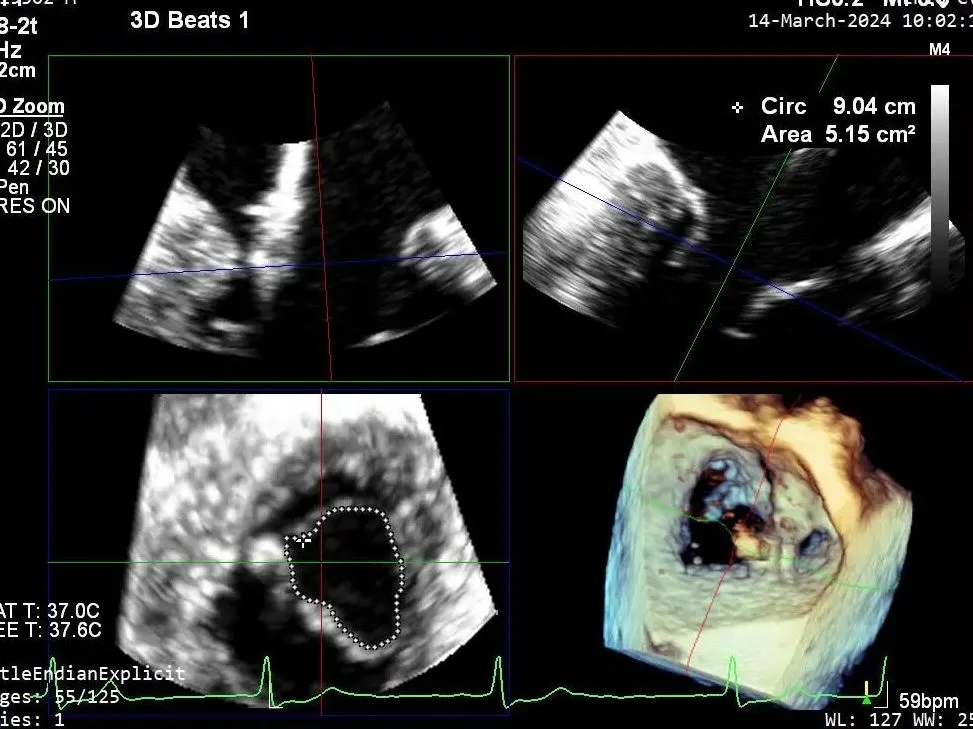

二尖瓣后叶活动受限,呈房源性栓系,以P3区为重,二尖瓣前叶假性脱垂,二尖瓣瓣环前后径49mm,左右径40mm。

PISA法测r=12mm,EROA=0.72cm2,RVOL=100ml,RF 26%。LVEDD 57mm,左房71*59*77mm,右房55*69mm,LVEF 70%。

释放瓣膜夹后评估,二尖瓣呈双孔,外侧仍有残余反流

第二个瓣膜夹释放后评估,二尖瓣呈双孔,外侧仍有残余反流

第三个瓣膜夹释放后评估,释放后评估,二尖瓣呈双孔,组织桥张力合适,瓣膜夹轴向与二尖瓣闭合线垂直,无残余反流